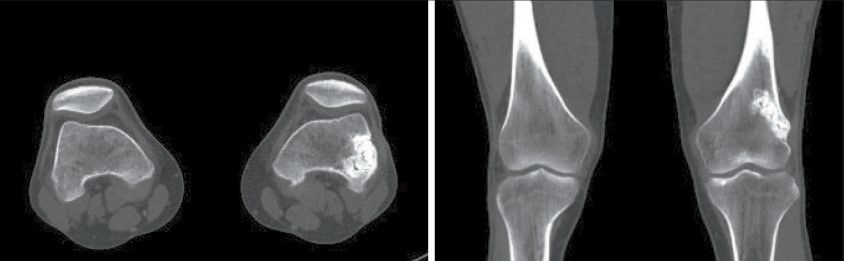

3. Рис. 3. СКТ коленного сустава. Зона реконструкции и ремоделирования в области ранее резецированного участка кости слева. Примечание: рисунок выполнен авторами | |